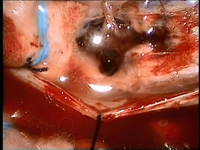

Hidrosefali tedavi edilmezse, beyin omurilik sıvısının (BOS) birikmesi nedeniyle beyin dokusunda baskı oluşur ve bu durum çeşitli komplikasyonlara yol açabilir. Uzun vadede, hidrosefali ciddi nörolojik sorunlara neden olabilir. Bunlar arasında motor fonksiyon bozuklukları, yürüyüş problemleri, denge kaybı, görme ve işitme sorunları, bilişsel gerileme ve hafıza kaybı sayılabilir. Ayrıca, hastanın yaşam kalitesi önemli ölçüde düşebilir; günlük aktivitelerini yerine getirme yeteneğinde azalma, sürekli baş ağrıları, bulantı ve yorgunluk gibi belirtiler ortaya çıkabilir.